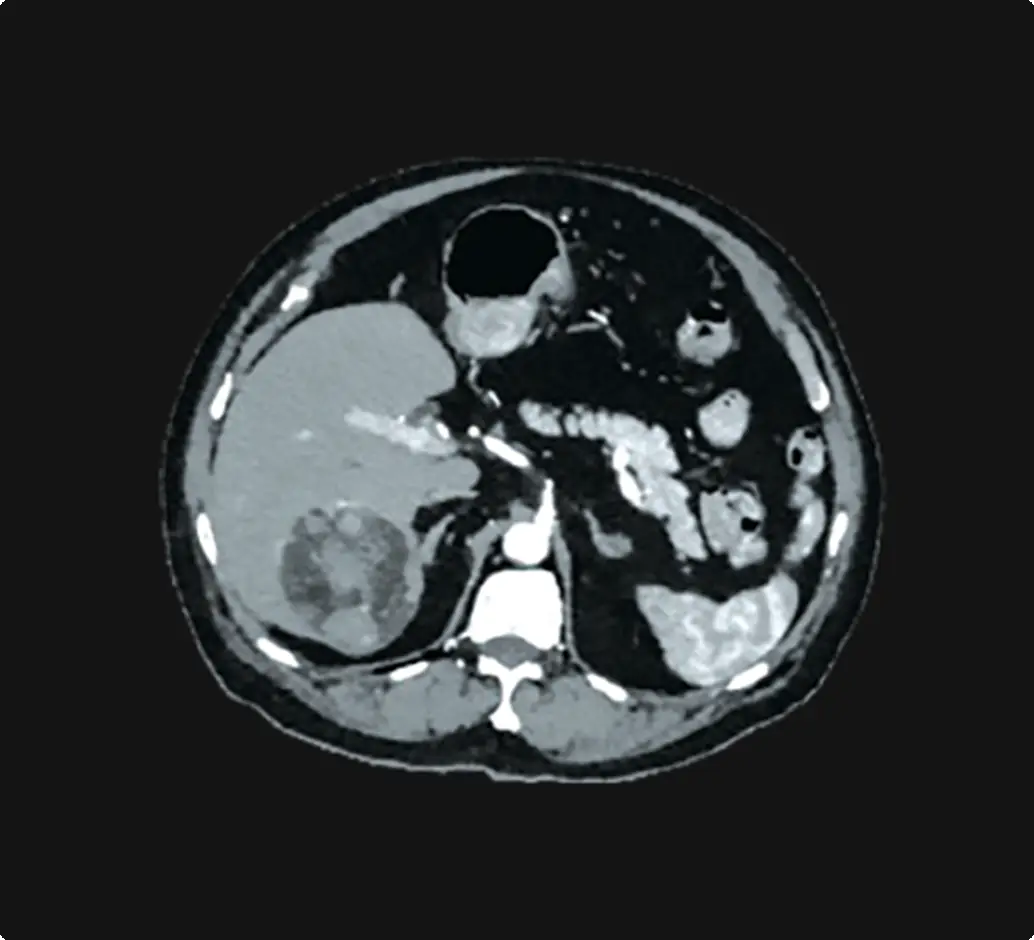

Multiple tumors can cause additional challenges

It can be difficult to deliver adequate treatment while minimizing injury to normal liver in patients with multiple tumors.3